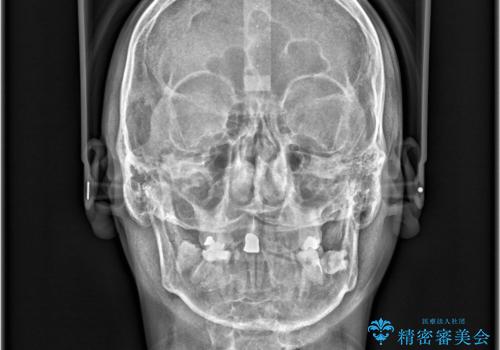

- 「八重歯と歯のでこぼこを治したい」を主訴に来院された患者様です。

歯は抜かずに奥歯の遠心移動とIPRで八重歯とでこぼこを改善しました。

左上3番は保険治療(CR)の劣化による二次カリエスになっていますので、後日治療予定です。